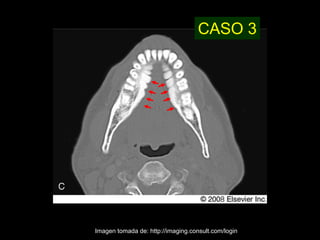

CASO 3

Imagen tomada de: http://imaging.consult.com/login